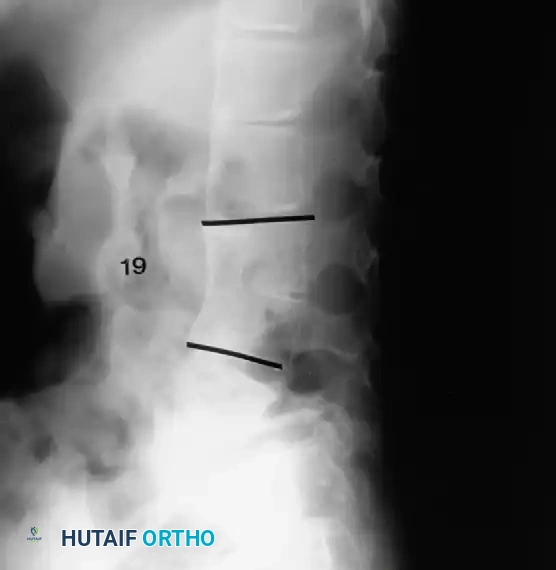

Two-year-old child with type I congenital kyphosis

Detailed anteroposterior (AP) and lateral radiographs are essential. Flexion and extension lateral views help determine the rigidity of the kyphosis and identify any compensatory hypermobility or instability in adjacent segments.